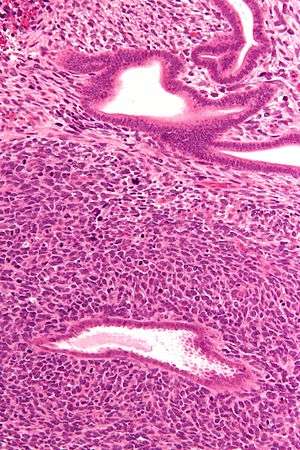

Low mag.

Intermed. mag.